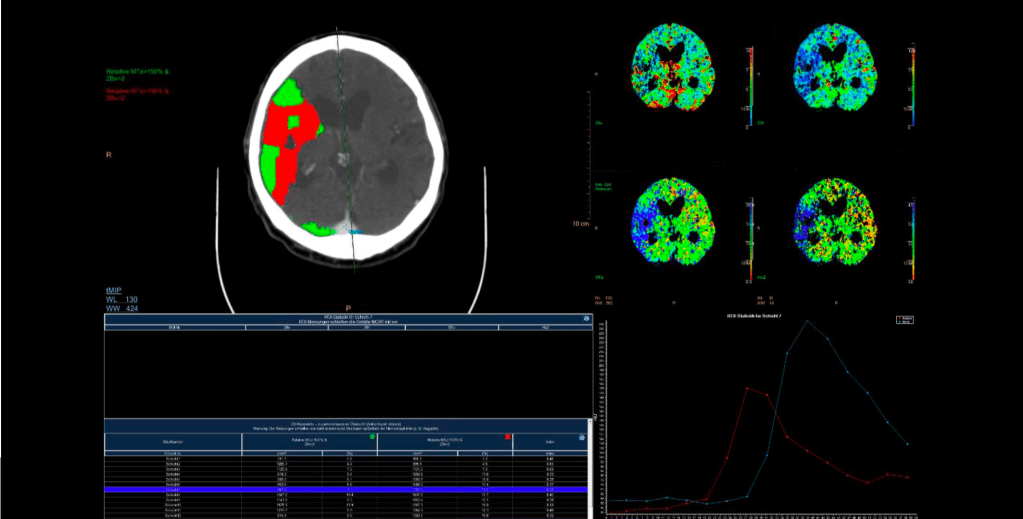

Typischerweise werden 40 ml Röntgen-Kontrastmittel mit relativ hoher Infusionsgeschwindigkeit (5 ml/s) infundiert. Dann wird durch repetitive CT-Messungen das An- und Abfluten des Kontrastmittels im Kopf gemessen, was über den Anstieg der Hounsfield Unit-Werte ja sogar quantifiziert werden kann. Dies macht man in den Arterien, den Venen und im Parenchym. Es entstehen bei den üblichen Protokollen ca. 30 CT-Aufnahmen hintereinander, welche alle 2 Sekunden angefertigt werden, so dass eine CT-Perfusionsmessung in der Regel ziemlich genau eine Minute dauert. Es gibt allerdings auch andere Protokolle und bei einer schlechten Pumpfunktion des Herzens ist das (so zeigt es auch die klinische Erfahrung) auch gar nicht so selten zu kurz. 30 CT-Aufnahmen hintereinander verursachen eine nicht unerhebliche Strahlenbelastung, auch wenn die Dosis pro CT-Messung schon reduziert wird (was man auch an der Bildqualität der CT-Perfusionsmessungs-Bilder sehen kann). Es entstehen dann zwei Messparameter (und das sind auch die entscheidenden, die anderen beiden kann man für die meisten Fälle erst einmal in den Skat drücken). Das sind die mittlere Transitzeit oder mean transit time oder MTT und das ist das zerebrale Blutvolumen oder cerebral blood volume oder CBV. Die MTT beschreibt die Zeit, die das Kontrastmittel zum An- und Abfluten im Hirngewebe braucht und ist am Ende eine Korrelation aus der Messkurve aus der Arterie und des Hirngewebe selber. Die CBV ist so ein schöner area under the curve-Messwert und vergleicht KM-Aufnahme im Hirnparenchym (unter der Kurve des An- und Abflutens) mit dem An- und Abfluten in den Venen (und hier auch als Fläche unter der Kurve). Die Idee ist dann, dass die CBV angibt, wo überhaupt noch Kontrastmittel hinkommt (eben nicht in den Infarktkern) und die MTT, wo das Kontrastmittel langsamer an- und abflutet, nämlich im Risikogewebe. Dazu kommt, dass im Risikogewebe durch die Weitstellung aller Kollateralgefäße das CBV meistens normal bis erhöht ist. Die beiden anderen – eher nicht so entscheidenden – Parameter sind dann noch die Halbwertszeit oder time to peak oder TTP, was einfach die halbe MTT bis zum Scheitelpunkt ist und der zerebrale Blutfluss oder CBF, was der Quotient aus CBV und MTT ist. Dies bedeutet, dass man – nach der Idee hinter der CT-Perfusionsbildgebung – dann in der CBV den Infarktkern und in der MTT die Penumbra sehen würde und kleiner Infarktkern und große Penumbra dann unsere Mismatch-Analogie darstellen würde.

Für den anspruchsvollen Connaisseur sei noch erwähnt, dass die TTP in erster Linie im CT-Protokoll auftaucht, weil sie in der MRT-Perfusionsbildgebung relativ viel benutzt wird und dass das ganze (die MRT-Perfusion noch mehr, das werden die Freunde der CT-Perfusion auch nicht müde zu betonen), daran krankt, dass es keine allgemein akzeptierten und standardisierten Messwert-Grenzen gibt, da das Ergebnis der Perfusionsbilder relativ stark vom Gerät, seinen Einstellungen, der Software, dem Hersteller, dem Patienten und seiner kardinalen Pumpfunktion usw. abhängt. Das führt dann oft zu solchen Aussagen wie: “Aber hinten links ist es doch irgendwie ein bisschen blauer in der MTT“. Ganz grob konnte man sich darauf einigen, dass eine MTT von 4-6 Sekunden normal ist und dass eine Verdoppelung der MTT (und/oder der TTP) für eine signifikant schlechtere Perfusion spricht. Für den CBF gibt es sogar eine Dreiteilung: > 50 ml/100 g Hirngewebe ist normal, bei < 20 ml/100 g Hirngewebe liegt eine ischämische Situation vor und unter 10 ml/100 g Hirngewebe eine strukturelle Infarzierung. Beim CBV muss man wissen, dass im Kortex typischerweise mehr Blut ist als im Marklager (was auch irgendwie nicht verwundert), da geht man physiologischerweise von 5-6 ml/100 g Hirngewebe im Kortex und von 2-3 ml/100 g Hirngewebe im Marklager aus. Bei einem kortikalen CBV von weniger als 2 ml kann man einen Infarktkern annehmen. In der hinteren Strombahn, in der ja langsamere Flussgeschwindigkeiten vorherrschen, sind vor allem die MTT- und TTP-Werte deutlich länger.